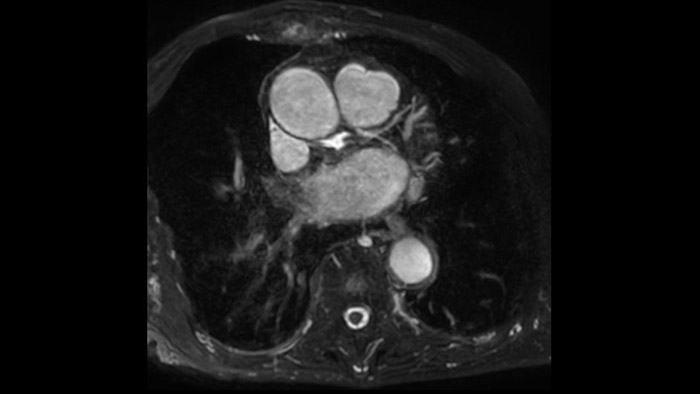

Diagnostic and prognostic utility of cardiac MR is increasing. Assess the anatomy and function of the heart using cine acquisitions, acquire information about perfusion and viability of the cardiac tissue, visualise potential edema with black blood sequence, access and even quantify tissue characterisation with CardiacQuant.

IntelliSpace Portal MR Caas5,6 Strain7 assists in patient diagnosis and monitoring by providing global strain parameters such as global longitudinal strain (GLS), global circumferential strain (GCS), and global radial strain (GRS), using short and long axis MR images, as well as describing the myocardium deformation- such as shortening, thickening, and lengthening during the cardiac cycle.